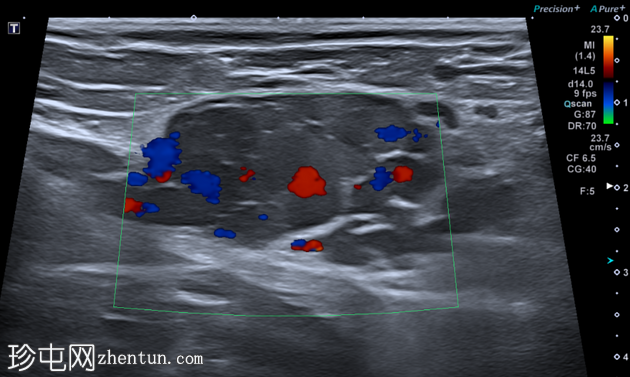

横切面

虽然本次图像未达到最佳效果,但彩色多普勒显示内部血流信号增强,Valsalva动作后血流信号增加,证实该结构为静脉性质。